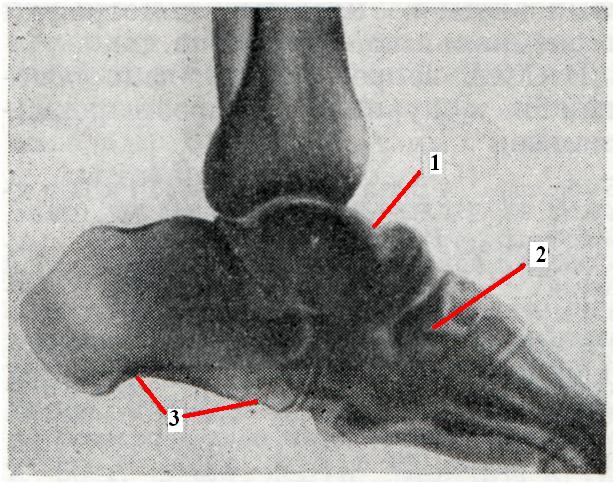

Рис. 3.

Артропатия при спинной сухотке. Деструктивные изменения в костях предплюсны. Патологические внесуставные переломы таранной (1), ладьевидной (2), пяточной (3) костей (рентгенограмма).

Внесуставные переломы особенно часты при спинной сухотке (рис. 3), а лоозеровские зоны перестройки (смотри Лоозера зоны) — при сирингомиелии. Оба осложнения характеризуются образованием массивной периостальной костной мозоли.

Рентгенодиагностика. Для артропатии типичны следующие основные рентгенологические признаки: рассасывание суставных концов костей (остеолиз), обезображивание их в связи с распадом костной ткани и бесформенными периостальными костными разрастаниями, остеосклероз, внутрисуставные и внесуставные патологические переломы и зоны перестройки в костях, беспорядочно расположенные параартикулярные окостенения и обызвествления, патологические вывихи и подвывихи. Своеобразной чертой артропатии является несоответствие между относительно мало нарушенной функцией сустава и грубыми морфологическими изменениями в нем. В связи с продолжающимся функционированием сустава суставные концы отшлифовываются, а отдельные костные отломки превращаются в суставные мыши.